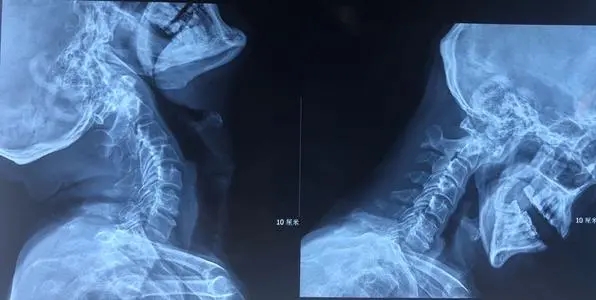

1.2.脊柱X線平片:常見椎弓根破壞、變薄及變形;椎弓根間距增寬,椎間孔擴(kuò)大;椎體后緣破壞、凹陷,椎管前后徑增大;椎管內(nèi)出現(xiàn)斑點(diǎn)狀鈣化灶、椎旁腫瘤影等。